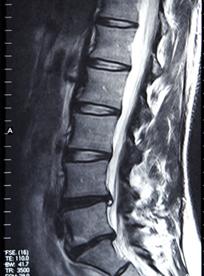

说这个问题之前,我们先来看一下什么是椎间盘?我们人体的躯干(脊柱)是由26块叫椎骨的骨头(下图浅黄色部分)组成的,在这26块骨头之间,有很多柔软的圆盘,就是椎间盘(下图白色+蓝色部分)。椎间盘具有缓冲和固定的作用,但是随着年龄的增长,椎间盘会分解和退化,会失去它的缓冲作用。如果受到过度压力,椎间盘被挤压后,就会压迫神经,或者纤维环破裂后里面果冻状的髓核漏出,刺激的神经,引发局部组织出现炎症,进而导致腰部疼痛、麻木等一系列症状,这就称为腰椎间盘突出症(以下简称“腰突症”)。